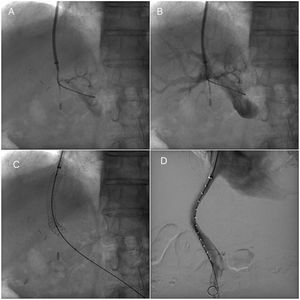

Transjugular intrahepatic portosystemic stent procedureTIPS procedures were conducted by vascular and interventional radiologists and were submitted by the Hepatology unit. The TIPS procedure was performed under sedation controlled by anesthetists. Through a transjugular venous approach, the hepatic vein was punctured and shunt was performed with e-PTFE-covered stents insertion (Viatorr Controlled Expansion Endoprosthesis, Gore) and was dilated to 10mm (Internal diameter was 8–10mm, graft lined length was 4–8cm and graft unlined length was 2cm). In Fig. 1, fluoroscopic image shows TIPS place procedure. Post-intervention Doppler ultrasonography was carried out the day after TIPS implantation to assess stent patency and rule out any complications.

Transjugular intrahepatic portosystemic shunt (TIPS) procedure. (A) Portal venogram after successful puncture from the hepatic vein. (B) Portal venogram after catheter has been advanced into the main portal vein shows normal portal vein bifurcation and intrahepatic branches. (C) Fluoroscopic image demonstrates full deployment of the stent graft. (D) Fluoroscopic image shows flow into the liver and through the stent graft.